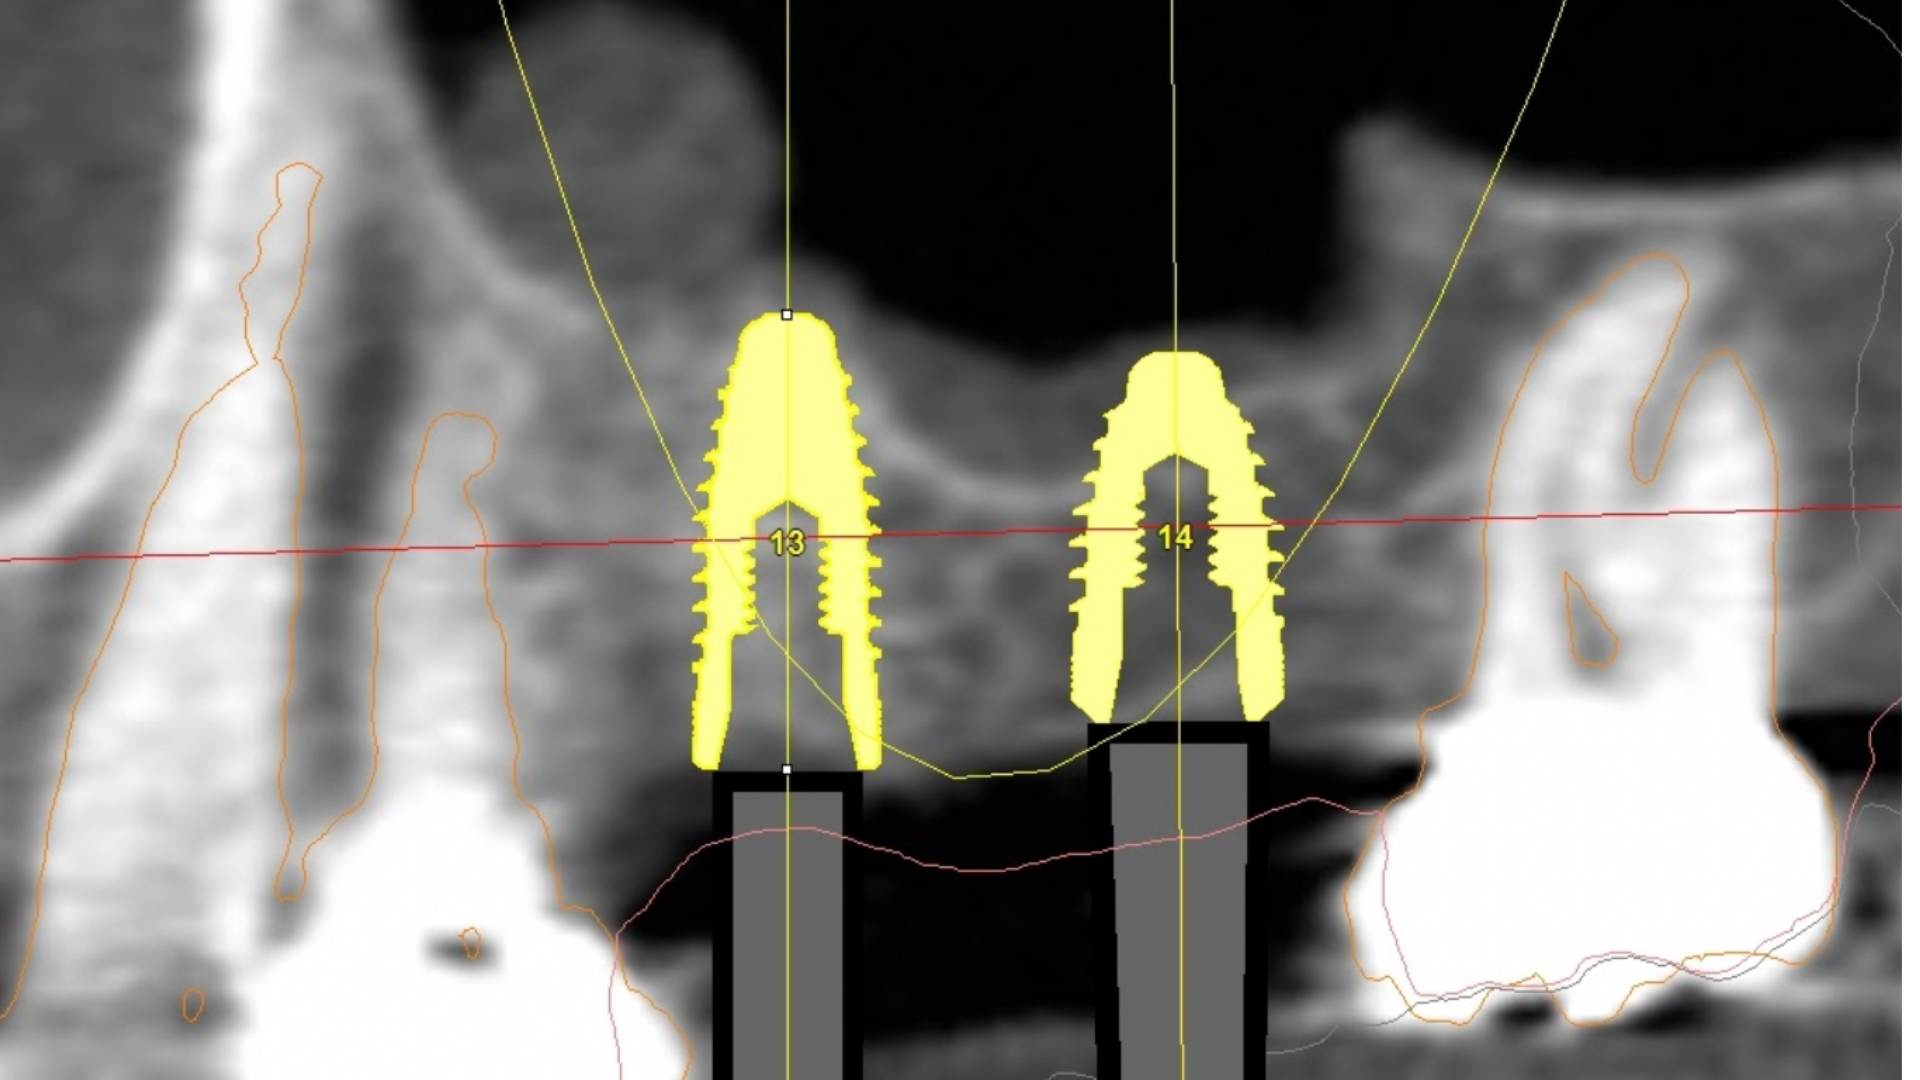

- How to diagnose the exact sinus lift method for each implant patient

Effective Planning & Execution

- When a crestal sinus lift is indicated.

- When a lateral window sinus lift is indicated

- What red zones must be avoided when doing lifts.